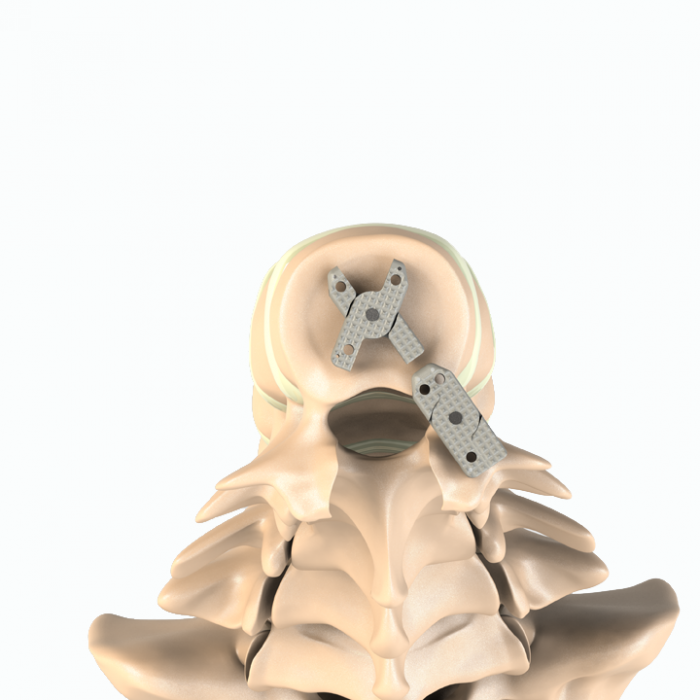

Aditus Lumbar Xlif Cage

- Anatomical Design

- Easy to Place within Disc Distance and Thanks to Elliptical Front Design

- Applicability of Posterior, Posterior Lateral or Extra Lateral from Disc Distance